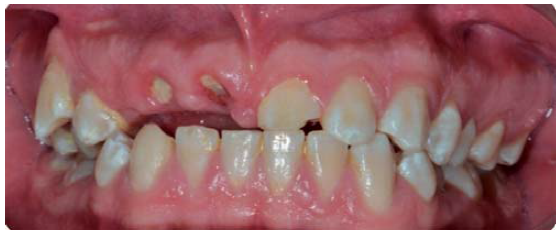

Paciente de sonrisa gingival que presenta fractura complicada de corona del diente 21 en el tercio medio coronal (Figura 3) y del diente 12 en el tercio cervical (Figura 4), fractura complicada de corona y raíz del diente 11 (Figura 5); gingivitis inducida por placa dentobacteriana (Figura 7), trasposición de los dientes 13 y 14, anodoncia verdadera de los dientes 15, 35 y 45, presentando los dientes temporales 55, 75 y 85.

Control periodontal durante el inicio del tratamiento de ortodoncia

El paciente fue citado para realizar el control personal de placa y darle indicaciones de cepillado con la actual aparatología ortodóntica (Figura 14).

Durante esta cita de control periodontal, se realizan radiografías dentoalveolares, en las que se observa una resorción radicular, la cual se puede atribuir a una respuesta inflamatoria del ligamento periodontal como respuesta al traumatismo o a los movimientos ortodónticos (Figura 15).